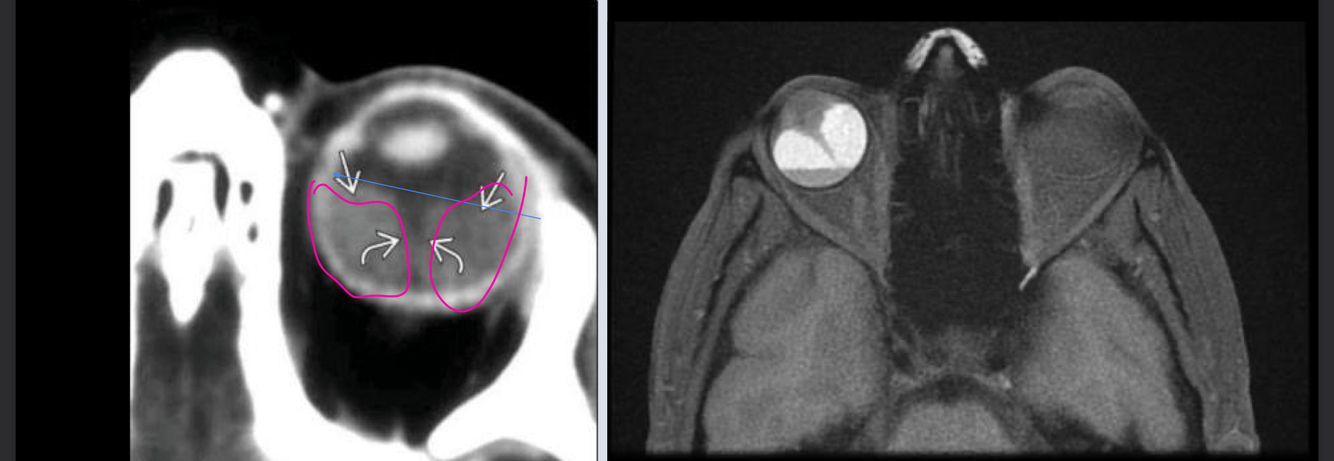

Que se ve en la imagen de orbitopatia tiroidea?

A

Agrandamiento BILATERAL de los musculos extraoculares

Tc-> aboradar enf no complicada y cirugia

RM-> decidir tratamiento y compromiso del nervio óptico

Que es?

TC ORBITOPATIA TIROIDEA

* Agrandamiento de los musculos extraoculares

* Exoftalmos

* nervio optico estirado

RM ORBITOPATIA TIROIDEA

T1: muculos grandes

T2: aumento de señal en musculos agudos/Baja en cronico